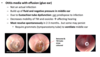

what is glue ear?

characterised by a collection of fluid in the middle-ear cleft

cause: Enlarged adenoid tonsils – these are found where the Eustachian tube meets the nasopharynx so if they are inflamed, the Eustachian tube can be blocked

pathophysiology of glue ear?

If EU tube is blocked, it can stop air from getting into the middle ear, causing a vacuum that draws fluid into the area, this fluid becomes thick & glue-like overtime and prevents ossicles from moving!

treatment of glue ear

mostly resolves on its own! If not, surgeoun will make an incision in the typmanic memebrane and drain the fkuid, then he will place a GROMMET, that allows are to move in and out of the middle ear

it evetually falls out after 2-3 minths and must be replaced

complication of Grommet insertion

tympanosclerosis